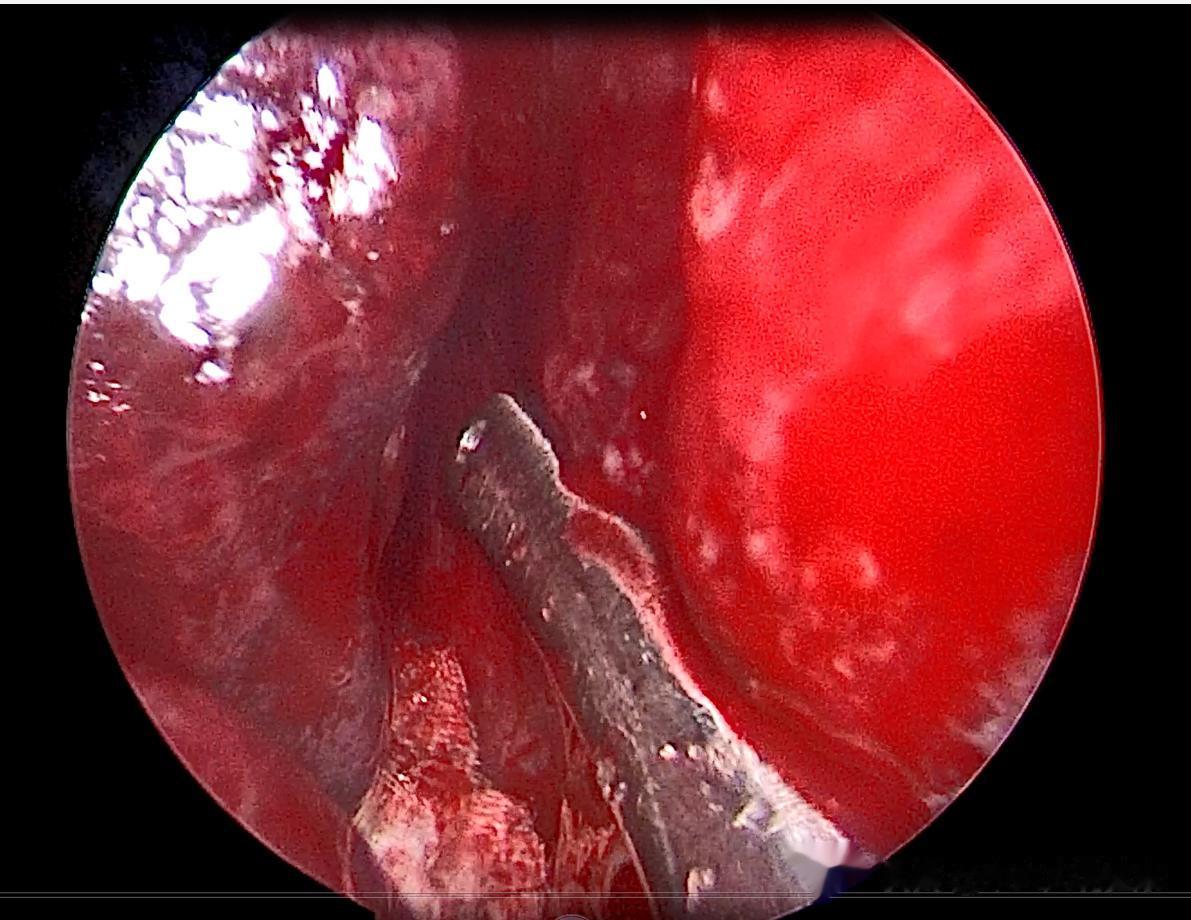

下午4点多快下班了,我接到紧急支援电话——作为二线医生,处理这种棘手病例,是义务,更是义不容辞的责任。我赶到时,患者情绪焦躁,血压持续居高不下,情况危急到容不得半点耽搁。紧急联系手术室,急诊全麻探查止血,可麻醉伊始,患者血压再次飙升、心率失控,手术全程凶险万分。内镜下可见,他右侧鼻腔嗅裂区、中鼻道、下鼻道多处渗血,之前反复多次的检查早已破坏了创面,根本无法有效找到原始出血点。

骑虎难下之际,我只能当机立断,用双极电凝对所有可疑出血点逐一烧灼,再用油纱条彻底填塞鼻腔。全程神经高度紧绷,手心全是冷汗,生怕漏过一个出血点,生怕血压骤变引发意外。万幸,术后出血止住,患者转回心内科控制血压,手术结束太阳已然西下。5日后再取出油纱条,一切平稳。